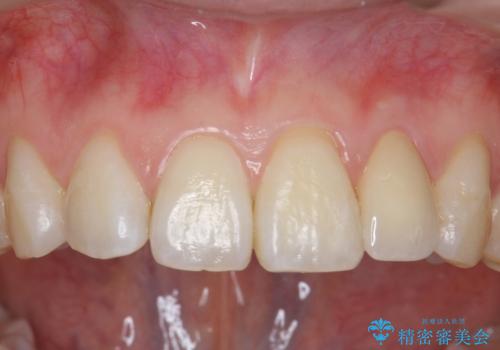

- 左上の前歯が生まれつき小さく、前に飛び出していました。

矯正治療で引っ込めてから、形を左右対称に整えるセラミック治療を行いました。

矯正治療と併用することで、劇的に見た目を改善することができます!